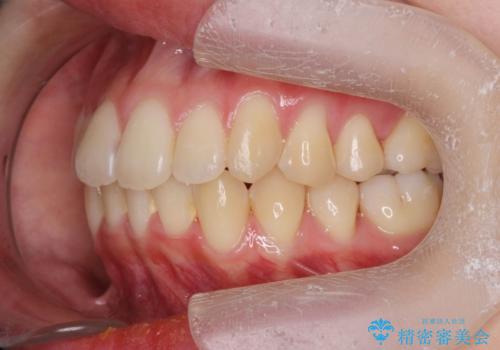

前歯のがたつきをマウスピース矯正できれいに!

- 目立つ前歯のがたつきを改善したい、と矯正治療を希望され来院されました。

今回の治療ではシミュレーションでしっかりと検討した結果、下顎は前歯を1本抜去し仕上げる治療計画としました。